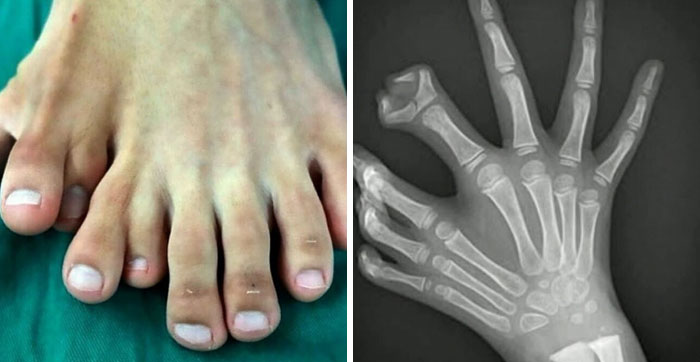

“Man Born With 9 Toes”: 41 Unsettling Medical Images That Show The Human Body At Its Strangest (New Pics)